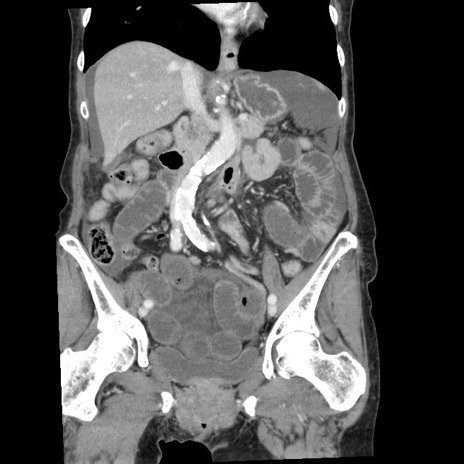

症例1(冠状断像)

【症例】80歳代女性

【主訴】腹痛

【現病歴】8時間前から腹痛あり来院。

【既往歴】糖尿病、脂質異常症、子宮体癌にて子宮全摘術

【身体所見】意識清明・会話良好だが腹痛で苦悶様、全腹部にわたって反跳痛と圧痛あり

【データ】WBC 13600、CRP 0.14、LDH 224、CK 90